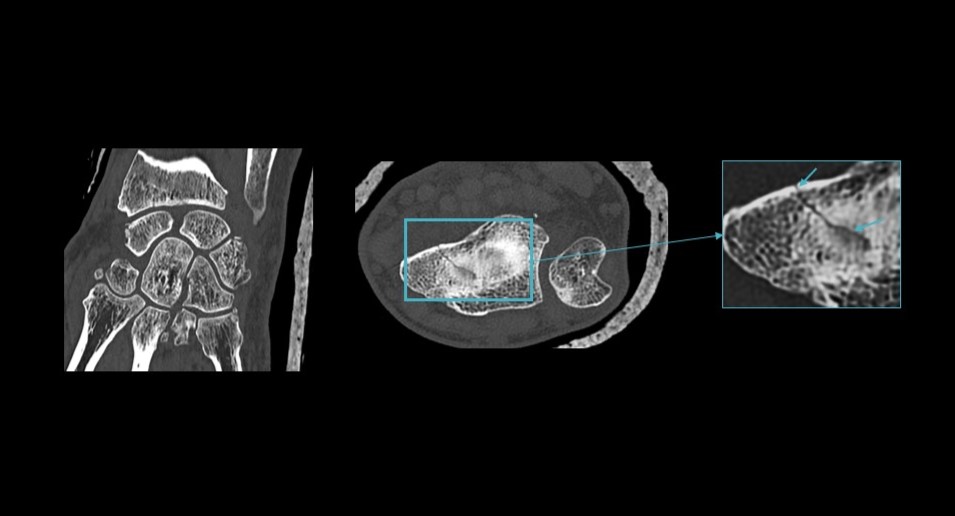

True Definition DL is designed to overcome these limitations by delivering exceptional clarity in high resolution CT imaging for bone and lung without compromising dose efficiency or acquisition speed. Its DL–driven approach enhances spatial resolution across multiple directions, integrates artifact suppression, and supports high definition (HD) mode to improve the visibility of fine anatomical structures such as small airways, pulmonary nodules, and trabecular bone patterns. This enhancement is critical for high-contrast imaging tasks, particularly in bone and lung imaging, where diagnostic confidence hinges on the ability to resolve subtle details.

Additionally, the solution offers a 1024 matrix for high resolution display, and chest imaging achievable in under one second, empowering clinicians to see more, diagnose with greater confidence, and expand access to high resolution imaging performance across a broader range of clinical settings.

“True Definition DL delivers exceptional spatial resolution for visualizing very small anatomical structures,” shares Dr. Stefanie Bitschnau, radiologist and collaborator at Radiomed. “In chest imaging, this level of detail is particularly valuable for assessing small airways, supporting earlier and more confident evaluation of interstitial lung disease. Additionally, the technology is highly beneficial in applications such as inner ear imaging with petrous bone scans, where it allows us to clearly visualize the auditory ossicles and detect erosions at an early stage. This improved definition also supports more confident fracture assessment.”